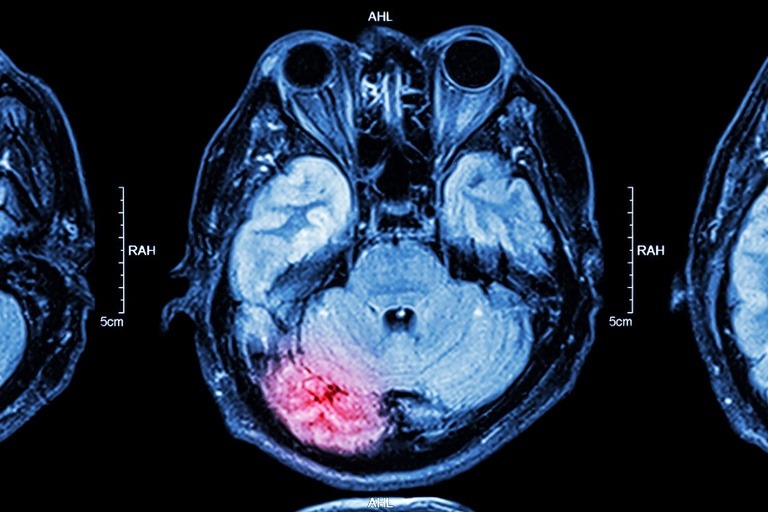

Em 2023, 12 brasileiros faleceram de AVC por dia. Detecção precoce pode evitar óbitos e sequelas nos pacientes. (Foto: Arquivo/EBSERH-UFU)

A campanha de conscientização Maio Vermelho, de prevenção ao acidente vascular cerebral (AVC), pode se tornar uma atividade permanente na cidade de Curitiba. É o que propõe um projeto de lei registrado na Câmara Municipal de Curitiba (CMC) no dia 24 de junho, que tramitará pelas comissões temáticas do Legislativo antes de ser votado em plenário.

Segundo dados da Associação de Registradores de Pessoas Naturais (Arpen Brasil), que reúne informações dos cartórios de Registro Civil, AVCs foram a causa da morte de 109.560 pessoas no país em 2023 - que equivale a 12 óbitos por dia no ano passado. O projeto de lei que cria a campanha permanente de prevenção em Curitiba é do vereador Pier Petruzziello (PP).